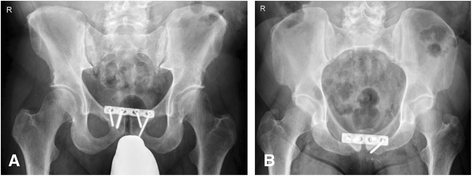

A 36-year-old otherwise healthy foreign male was found wincing in the vicinity of a ladder underneath a warehouse roof (height approximately 5 meters). Upon arrival of the EMS doctor the patient was able to maintain an open airway, the chest was stable und bilateral breath sounds were present. The patient was hemodynamically stable. The vitals were: respiratory rate 18/min, oxygen saturation 100 % without oxygen supply, heart rate 95 bpm, blood pressure 180/90 mmHg, blood sugar 135 mg/dl. Because of pelvic pain and suspected pelvic instability EPS was performed with the SAM Pelvic SlingTM II (SAM Medical Products®, Wilsonville, OR, USA). The Glasgow Coma Scale (GCS) was 14 (E4/V4/M6) and a fracture of the left lower leg was clinically diagnosed. After rapid sequence induction the patient was endotracheally intubated and a total crystalloid volume of 2000 ml was administered en route to our hospital. On admission we saw an intubated and mechanically ventilated patient. The vitals were: respiratory rate 12/min, etCO2 36 mmHg, oxygen saturation 100 % with FiO2 1.0, heart rate 80 bpm, regular sinus rhythm, blood pressure 150/90 mmHg. On physical examination no injuries to the cranium, chest or abdominal cavity were clinically evident. Sonography (Focused Assessment with Sonography in Trauma (FAST)) did not reveal any fluid collections and the pelvis had been immobilized as described above. The left lower leg was evidently fractured on clinical examination. The patient underwent whole-body CT that revealed bilateral lung contusions, a fracture of the right transverse process of the 5th lumbar vertebra, a right sided sacral fracture and superior and inferior pubic rami fractures (Fig. 4). The patient was taken to the operating room for supraacetabular external fixation of the pelvis and external fixation of the left lower leg. Upon arrival in the operating room provisional EPS was removed. Astonishingly, intraoperative fluoroscopy of the pelvis revealed a significantly wider pubic symphysis, suggestive of symphyseal disruption (Fig. 5). In due course, internal fixation of the anterior pelvis was performed together with iliosacral screw fixation. Intraoperative complete symphyseal disruption was confirmed warranting extended plate osteosynthesis of the pubic symphysis (Fig. 6). After converting the external fixation of the left lower leg to intramedullary nailing the further course of the patient was uneventful and the patient was repatriated on day eight after trauma.